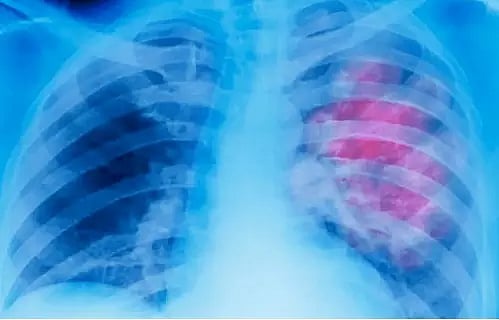

NEW DELHI: A newly developed artificial intelligence (AI) model could estimate one's age from their chest X-ray, new research published in The Lancet Healthy Longevity journal said.

The model can also signal chronic diseases such as hypertension and chronic obstructive pulmonary disease from the difference between estimated and chronological age, the research from Osaka Metropolitan University, Japan, said.

For age estimation, the AI model was trained using around 67,100 chest radiographs of 36,051 healthy individuals who underwent health check-ups between 2008 and 2021.

The model showed a strong correlation between the AI-estimated age and the chronological age of the individuals, the researchers found.

It was then trained to analyse the link between the AI-estimated age and each disease on additional 34,197 chest radiographs compiled from as many patients with known diseases.

In all, the model was trained on roughly 1,01,300 chest X-rays obtained from 70,248 participants across five institutions in Japan.

The difference between the individual's AI-estimated age and their chronological age was found to be strongly associated with chronic diseases such as hypertension, hyperuricemia (high uric acid levels in blood), and chronic obstructive pulmonary disease.

This meant, the researchers said, that higher the age the AI estimated, higher the likelihood of these individuals to have the aforementioned diseases.

Chest X-rays could thus be useful as a biomarker of aging and longevity, they said, because they can show not only the shape of features within the body, but also details of internal organs and bones.